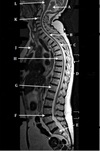

What is letter A?

CEREBELLUM

56

What is letter B?

SPINAL CORD

57

What is letter C?

CSF

58

What is letter D?

SPINOUS PROCESS

59

What is letter E?

S1 VERTEBRAL BODY

60

What is letter F?

INTERVERTEBRAL DISK SPACE

61

What is letter G?

12TH THORACIC VERTEBRAE

62

What is letter H?

7TH THORACIC VERTEBRAE

63

What is letter J?

SUPRASTERNAL NOTCH

64

What is letter K?

3RD CERVICAL VERTEBRAE

65

What is letter L?

PONS